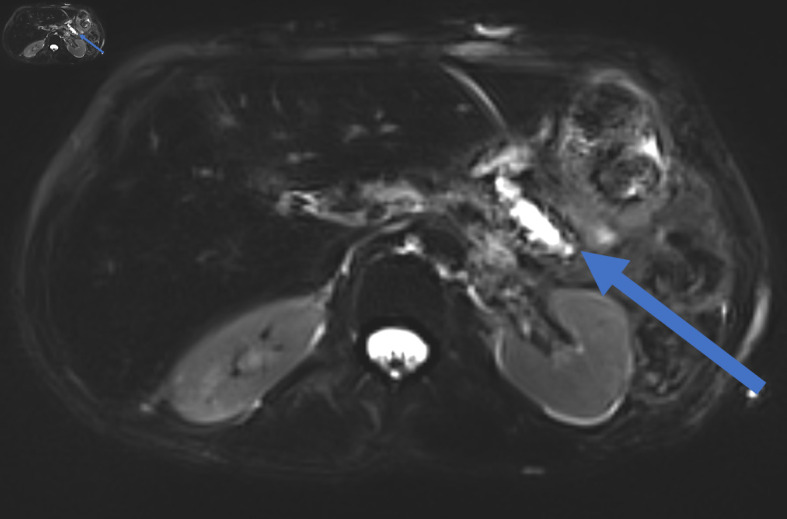

Pancreatoduodenectomy (PD) is a very complex and highly challenging operation for surgeons worldwide. It is the surgical procedure of choice for the management of benign and malignant diseases of the periampullary region. Although mortality rate following this complicated surgery has fallen to 1-3%, morbidity rate following PD remains high, with almost 30-40% of patients developing at least one complication. Postoperative pancreatic fistula (POPF) is one of the most common complications following PD. Therefore, Pancreatico-enteric anastomosis has been regarded as the "Achilles heel" of the modern, one-stage PD procedure. According to the International Study Group of Pancreatic Surgery (ISGPS), three types of POPF are recognized nowadays: biochemical leak, previously known as grade A POPF, grade B and grade C, with the latter being the most dangerous. Most POPFs, especially of the biochemical leak and grade B heal with non-operative management to recur later and present as an intra-abdominal abscess or pseudocyst, necessitating management by means of interventional radiology, endoscopy or surgery. These types of fistulas are undefined and occasionally intractable. Herein, we present two patients who presented with the aforementioned type of pancreatic fistula following duct occlusion PD. The first patient, a 53-year-old female patient, suffered from intolerance to oral feeding, severe weight loss and recurrent hospital admission, while the second patient, a 72-year-old patient, suffered from recurrent bouts of abdominal sepsis. Their management involved step-up approach, starting with non-operative management, followed by percutaneous drainage and operative treatment in the form of Puestow-like procedure (longitudinal pancreatojejunostomy), as a recourse due to the inadequacy of preceding therapeutic modalities.

Abstract Image